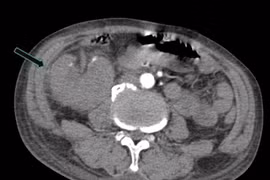

Đau bụng, vật vã người phụ nữ 67 tuổi viêm phúc mạc do thủng tạng rỗng

Bệnh nhân sốc nhiễm khuẩn nặng, phụ thuộc thuốc vận mạch (nhóm thuốc dùng để nâng huyết áp) liều cao, thở máy với oxy nồng độ cao và vô niệu hoàn toàn.